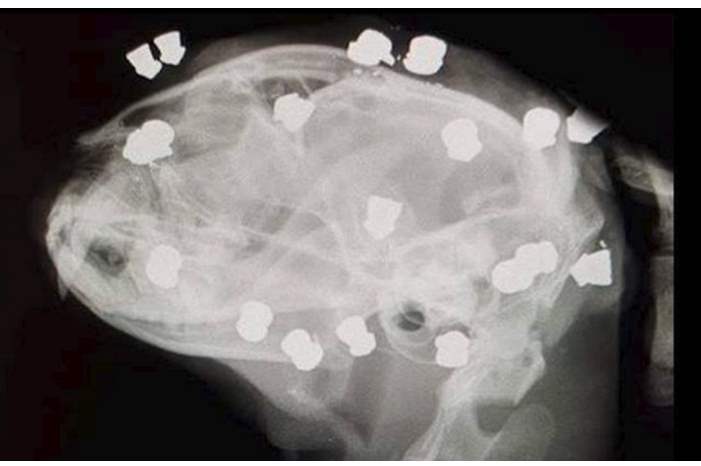

وعند إخضاع القطة إلى عمل جراحي عاجل، تبين وجود 18 طلقة هوائية مستقرة في وجهها ورأسها ورقبتها، في حين فقدت عينها اليسرى إثر الهجوم الوحشي.

وأشارت التحقيقات الأولية إلى أن المهاجم وجه الطلقات لرأس القطة، الواحدة تلو الأخرى، الأمر الذي سبب لها ألما رهيبا، وكذلك منعها من الهرب المبكر من أيدي الرجل.